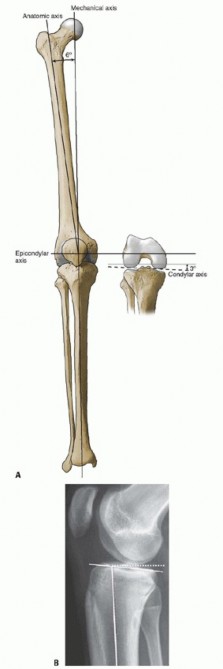

P ITFALLS Results of each type of alignment are technique dependent, and familiarity with each will reduce co…